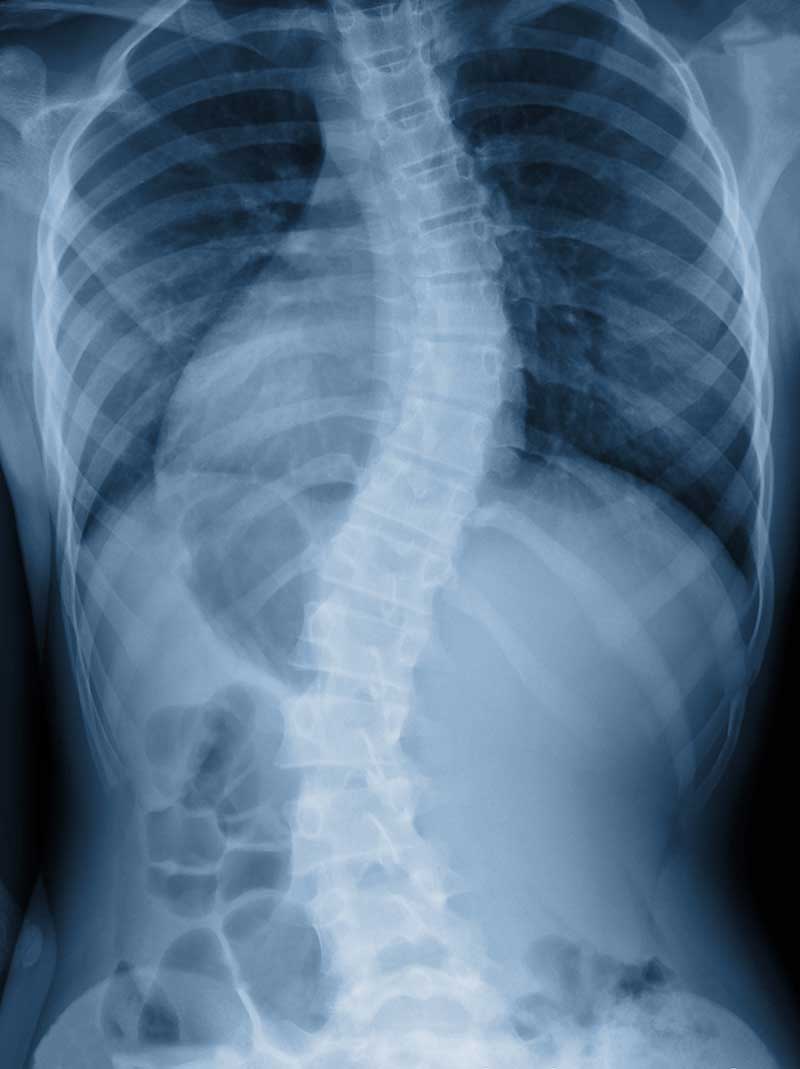

- Scoliosis

Scoliosis

When detected early, scoliosis can be managed and treated to prevent the problem from getting worse. With scoliosis, the spine has abnormal curvatures to the side or even twists. Most cases of scoliosis appear for unknown reasons as scoliosis tends to develop before puberty in adolescence, in children who previously had no spine issues.

Many cases of scoliosis do not require surgery or extensive treatment, but if the curvature becomes more severe, medical intervention may be needed. Scoliosis appears equally in boys and girls, but typically girls are more likely to develop significant curvature that warrants treatment.